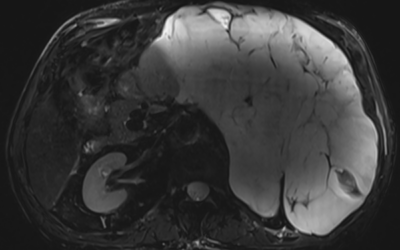

Caso de abdomen

Varón de 80 que consulta por dolor en hipocondrio izquierdo de dos meses de evolución y sensación de masa. El dolor aumenta ligeramente con la inspiración profunda.Comenta pérdida de peso hace 5 años que no ha progresado.Exploración Física: Abdomen blando y...